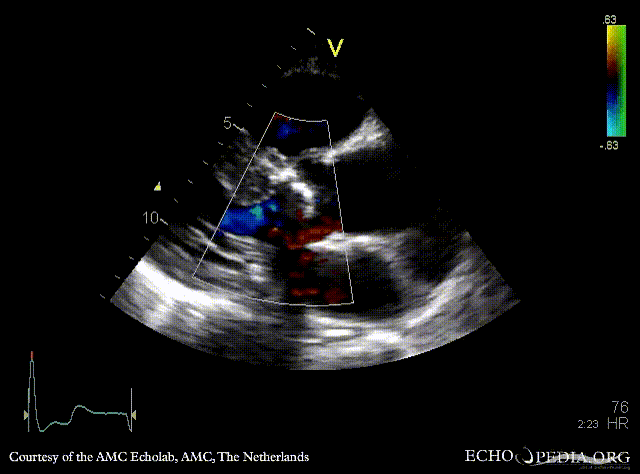

| <html5media height="350" width="279" autoplay="true" loop="true">File:E00774.mp4</html5media> | <html5media height="350" width="279" autoplay="true" loop="true">File:E00775.mp4</html5media> |

| PSAX: stenosis of aortic valve | PLAX with Color Doppler: high velocity transaortic flow, mild aortic regurgitation |